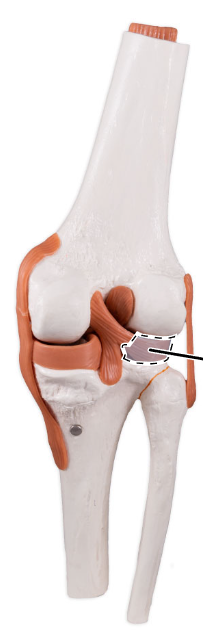

What ligament is shown here?

Medial (tibial) collateral ligament.

What ligament is shown here?

Medial (tibial) collateral ligament.